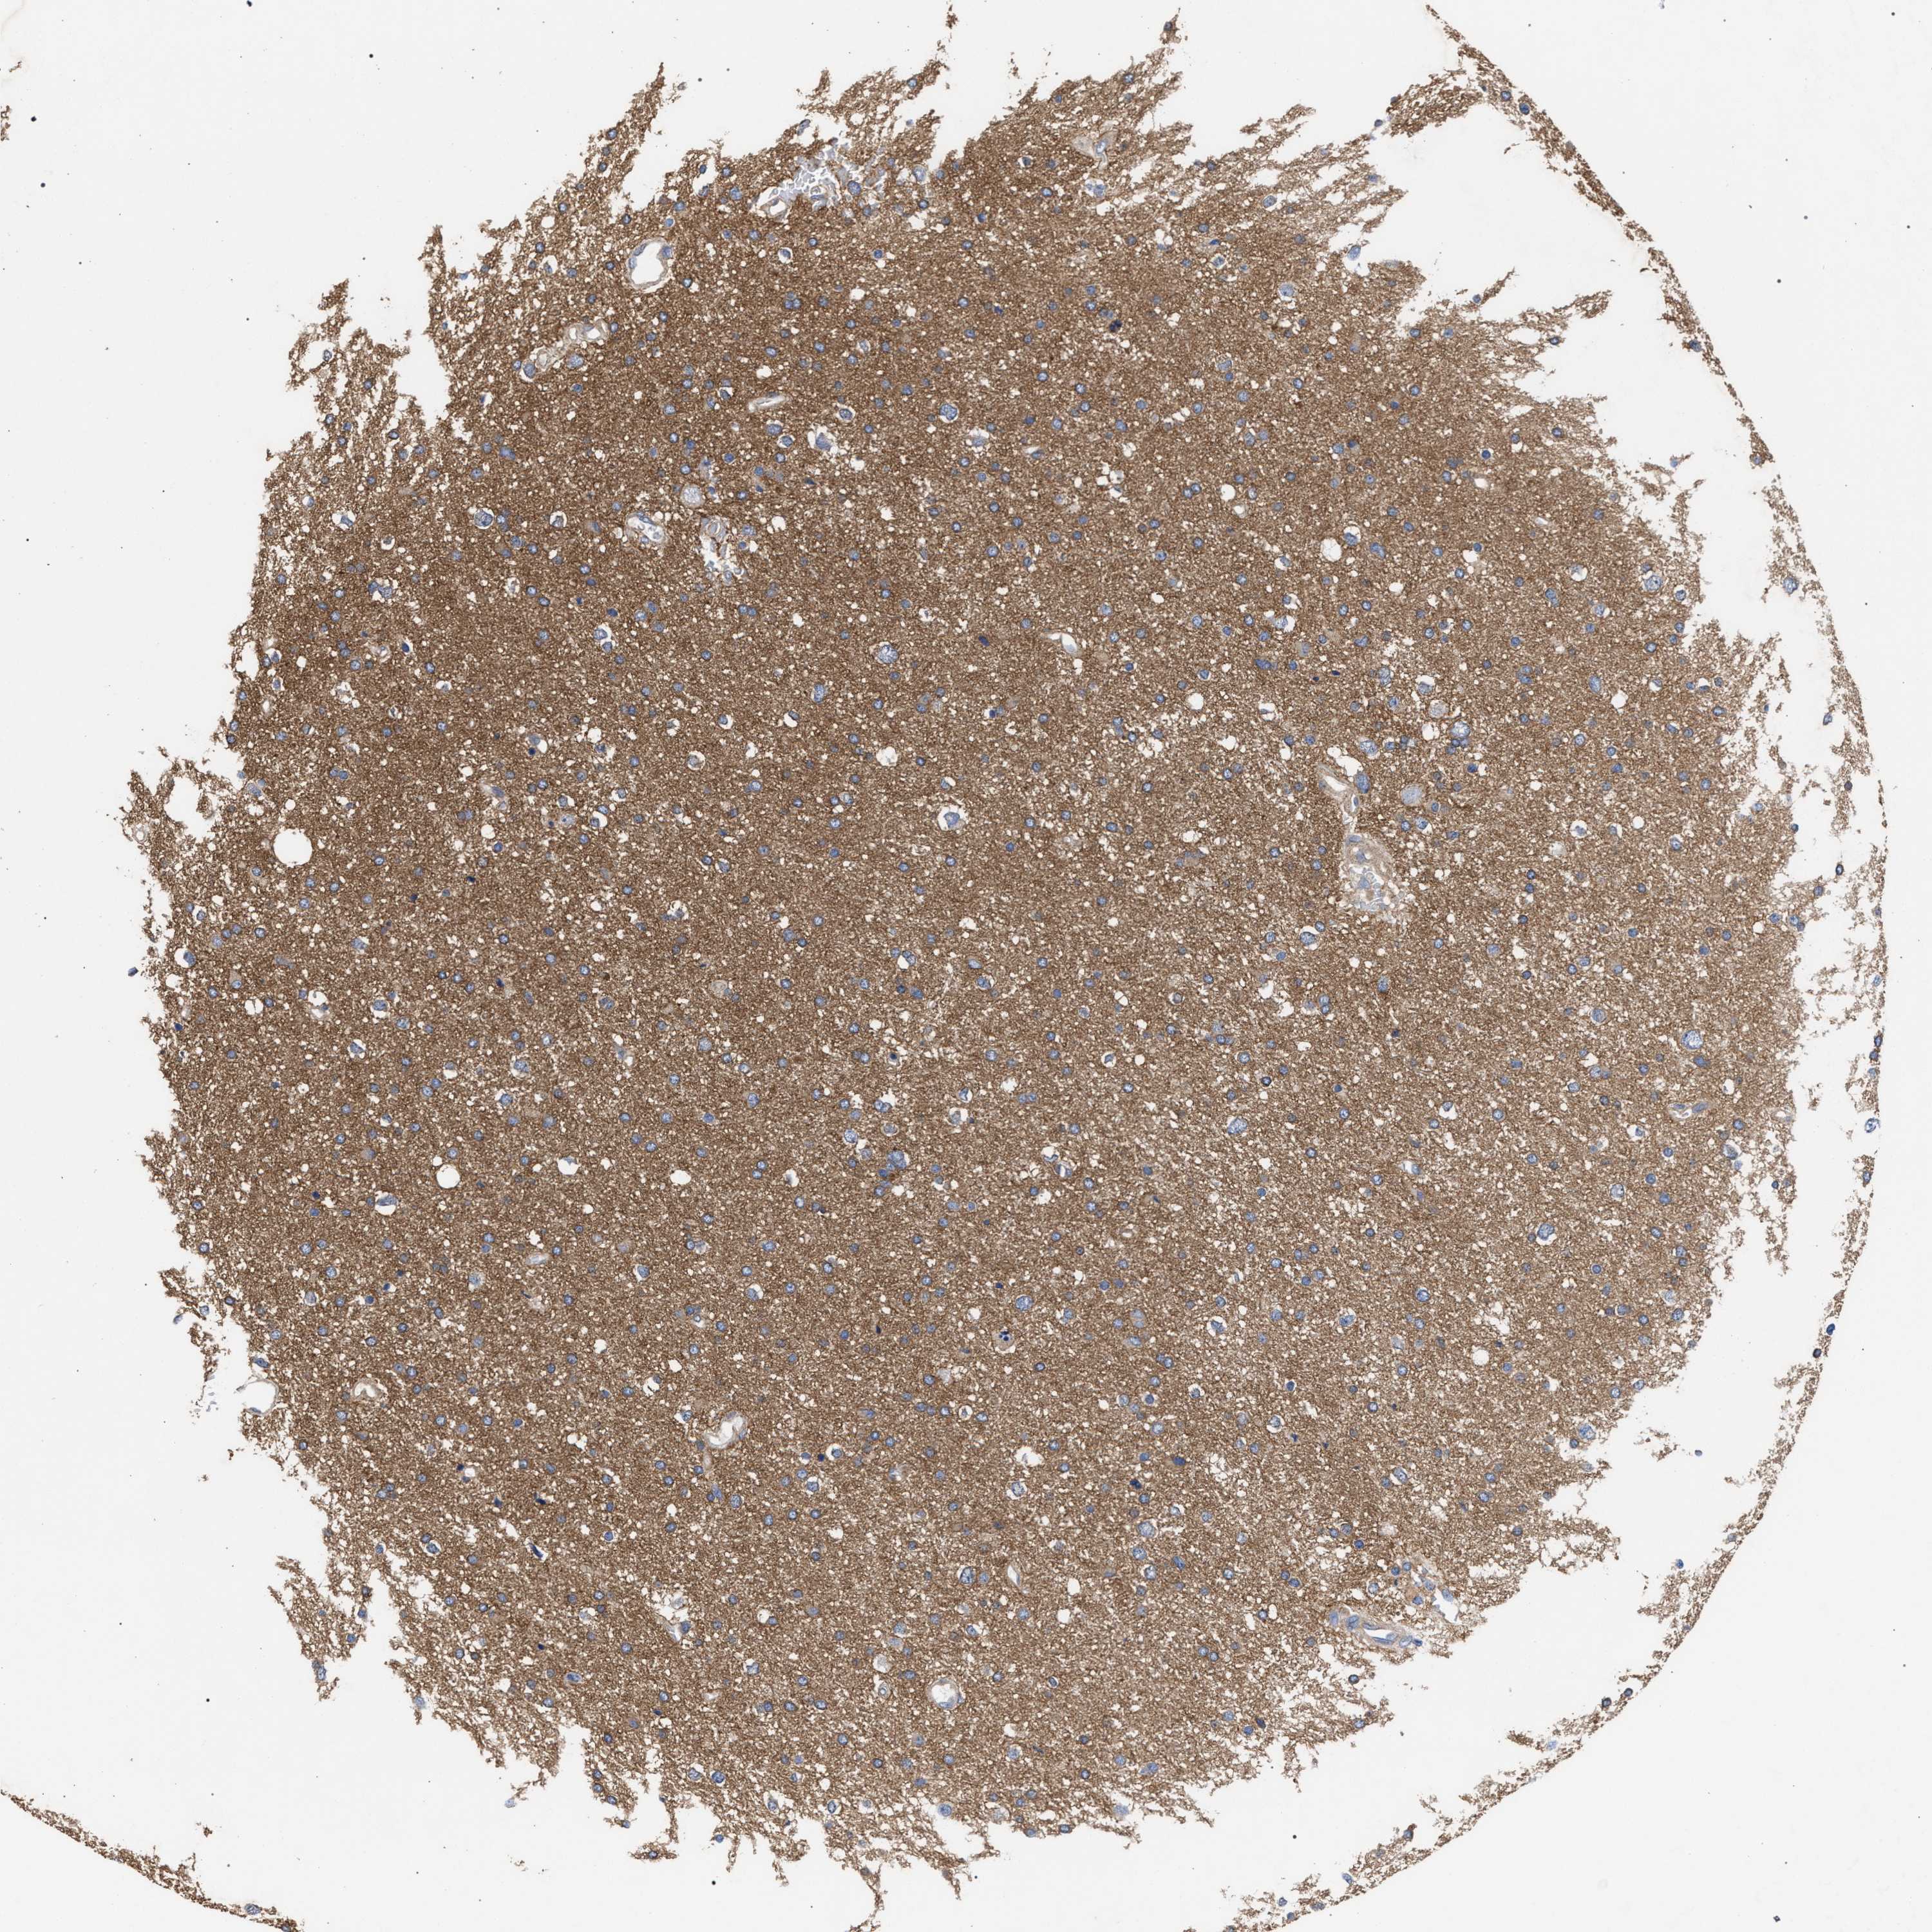

GLIOMA - Protein expressioni

A mouse-over function shows sample information and annotation data. Click on an image to view it in a full screen mode. Samples can be filtered based on level of antibody staining by selecting one or several of the following categories: high, medium, low and not detected. The assay and annotation is described here.

Note that samples used for immunohistochemistry by the Human Protein Atlas do not correspond to samples in the TCGA dataset.

Antibody stainingi

Antibody staining in the annotated cell types in the current human tissue is reported as not detected, low, medium, or high, based on conventional immunohistochemistry profiling in selected tissues. This score is based on the combination of the staining intensity and fraction of stained cells.

Each image is clickable and will lead to virtual microscopy that enables deeper exploration of all samples and also displays staining intensity scores, fraction scores and subcellular localization as well as patient and tissue information for each sample.

Antibody HPA021261

Antibody HPA021325

Staining

High

Medium

Low

Not detected

Intensity

Strong

Moderate

Weak

Negative

Quantity

>75%

75%-25%

<25%

None

Location

Nuclear

Cytoplasmic/membranous

Cytoplasmic/membranous,nuclear

Glioma, malignant, High grade

Glioma, malignant, Low grade